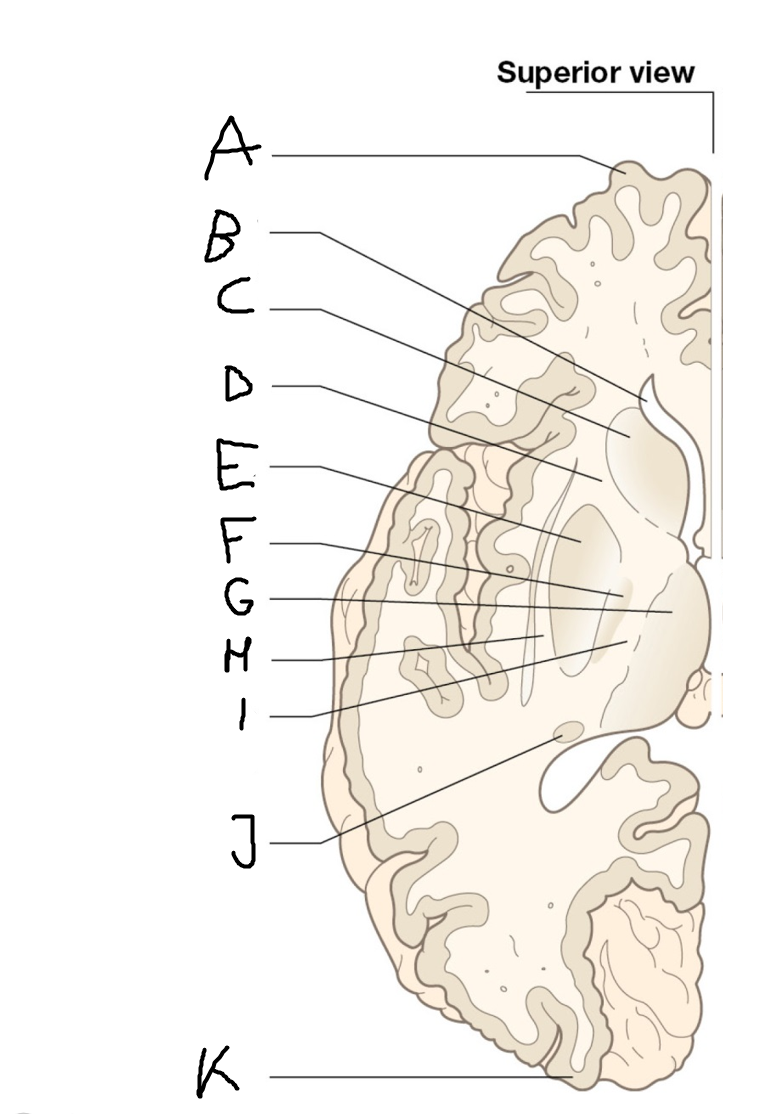

internal capsule (posterior limb)

B

anterior horn of lateral ventricle

C

head of caudate nucleus

D

internal capsule (anterior limb)

E

putamen

F

globus pallidus

G

Thalamus

H

External capsule

I

internal capsule (posterior limb)

J